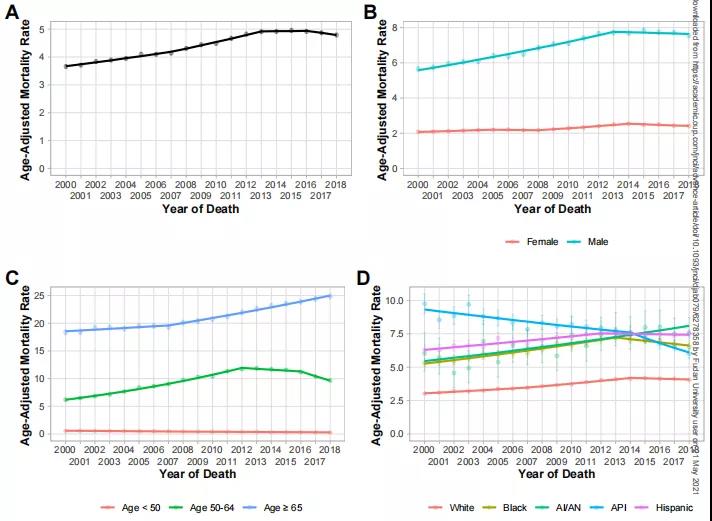

张宇华表示,门诊中首诊的肝癌患者只有20-30%有手术机会,剩余百分之七八十的首诊患者因为发现时已经是中晚期,很多已经没有了手术机会,而手术切除是肝癌患者目前唯一可能获得长期生存的治疗选择。

“这主要是肝癌的早期症状不是很明显。”张华宇说,其实,很多肝癌患者都有多年的肝脏疾病,最常见的就是乙肝,因为没有及时干预,日积月累才发展成肝癌。

“还有一部分肝癌患者是由脂肪肝发展而来的。” 张华宇说,长久以来,人们都以为肝癌很难治愈,尤其是中晚期,一旦被确诊,感觉是被判了死刑,“实际上,现在对于肝癌的治疗发展很快,有很多手段,除了手术之后,对那些初诊不能手术的患者,还可以采用转化治疗,包括介入治疗,靶向免疫治疗等等,也就是先“保守”治疗,将肿瘤缩小,再寻求手术切除的机会。”